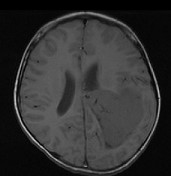

男,8岁,头痛伴呕吐,左侧眼视物不适5天,请根据所提供图像,选择最可能的诊断()

A.(左侧脑室)脑膜瘤

B.(左侧脑室)室管膜瘤

C.(左侧脑室)脉络丛乳头状瘤

D.(左侧脑室)胶质瘤

E.(左侧脑室)少突胶质细胞瘤

男,8岁,头痛伴呕吐,左侧眼视物不适5天,请根据所提供图像,选择最可能的诊断()

[单选题]男,8岁,头痛伴呕吐,左侧眼视物不适5天,请根据所提供图像,选择最可能的诊断()A .(左侧脑室)脑膜瘤B .(左侧脑室)室管膜瘤C .(左侧脑室)脉络丛乳头状瘤D .(左侧脑室)胶质瘤E .(左侧脑室)少突胶质细胞瘤